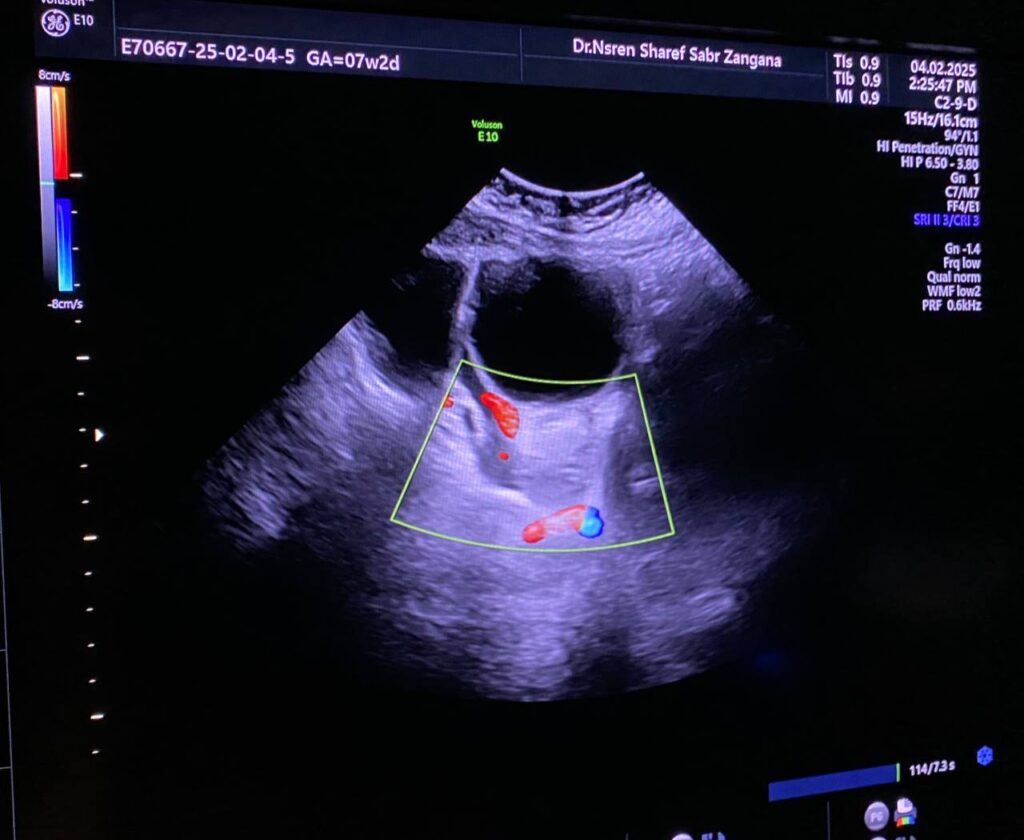

Left ovarian avascular cystic mass 71x68mm , with adjacent left adnexal mass 30x30mm , picture mostly of twisted ovarian pedicle , associated with free fluid >40ml , please for further study to excluded other pathology

Right ovary normal in size, no mature or dominant follicle

Lt ovary is enlarged and edematous, contains 7cm thin wall unilocular cyst “ORADS 1”, there is twisting of its vascular pedicle, picture of ovarian torsion.